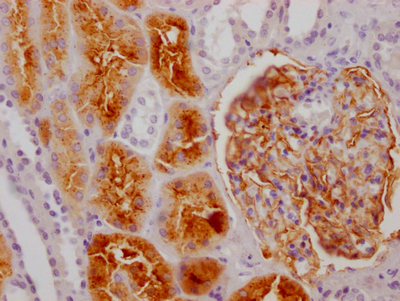

IHC image of CSB-RA552900A0HU diluted at 1:100 and staining in paraffin-embedded human kidney tissue performed on a Leica BondTM system. After dewaxing and hydration, antigen retrieval was mediated by high pressure in a citrate buffer (pH 6.0). Section was blocked with 10% normal goat serum 30min at RT. Then primary antibody (1% BSA) was incubated at 4℃ overnight. The primary is detected by a Goat anti-rabbit IgG polymer labeled by HRP and visualized using 0.05% DAB.

產(chǎn)品描述:ENPEP Recombinant Monoclonal Antibody(CSB-RA552900A0HU)是一款針對(duì)人源谷氨酰氨肽酶(ENPEP)的高特異性抗體,適用于酶聯(lián)免疫吸附實(shí)驗(yàn)(ELISA)和免疫組織化學(xué)(IHC)檢測(cè)。ENPEP是一種膜結(jié)合金屬蛋白酶,參與血管緊張素代謝和細(xì)胞黏附過程,其表達(dá)水平與血管生成、腫瘤微環(huán)境調(diào)控及心血管功能密切相關(guān)。本產(chǎn)品通過重組表達(dá)技術(shù)制備,經(jīng)嚴(yán)格驗(yàn)證可在IHC實(shí)驗(yàn)中清晰顯示ENPEP蛋白在石蠟包埋組織中的定位分布,推薦使用稀釋比例為1:50-1:200,實(shí)驗(yàn)數(shù)據(jù)表明其具有優(yōu)異的批間一致性、低交叉反應(yīng)性和高信噪比特性,能夠有效識(shí)別天然構(gòu)象的靶蛋白。該抗體適用于研究ENPEP在組織發(fā)育、腫瘤生物學(xué)或心血管疾病相關(guān)模型中的表達(dá)調(diào)控機(jī)制,為探索其在細(xì)胞外基質(zhì)重塑、病理微環(huán)境調(diào)控等領(lǐng)域的生物學(xué)功能提供可靠工具,滿足基礎(chǔ)科研中對(duì)蛋白定位及表達(dá)水平分析的需求。

組織特異性:Expressed in choriocarcinoma cancer cell lines (at protein level). Expressed by epithelial cells of the proximal tubule cells and the glomerulus of the nephron. Also found in a variety of other tissues.